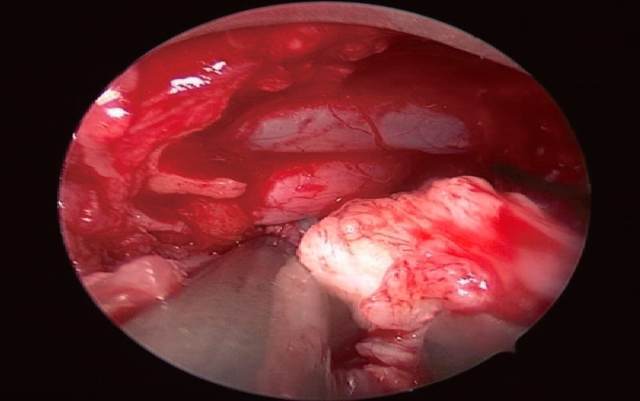

手术:手术采用内镜微创椎间盘显微切除术腰5骶1 (L5〜S1)。俯卧位,腹部垫空,消毒铺单,插入定位针透视确定手术间隙,取棘突旁开1.5cm于病变侧做长约1.8cm的纵向切口切开,逐级套管扩张,安装手术通道。连接摄像及显示系统,调节焦距及手术视野。清除术野中黄韧带表面的软组织,显示上位椎体椎板的下缘及黄韧带,部分咬除上位椎体的椎板下缘及关节突的内侧缘和黄韧带。显露部分硬脊膜及神经根,神经剥离子探查神经根受压及粘连情况。神经根拉钩将神经根牵向内侧,显露突出的椎间盘组织。切开纤维环,髓核钳取出病变的髓核组织,枪钳扩大神经根管及狭窄的侧隐窝,小心仔细分离粘连的神经根,冲洗手术视野。

下图为:内镜下摘除突出的椎间盘